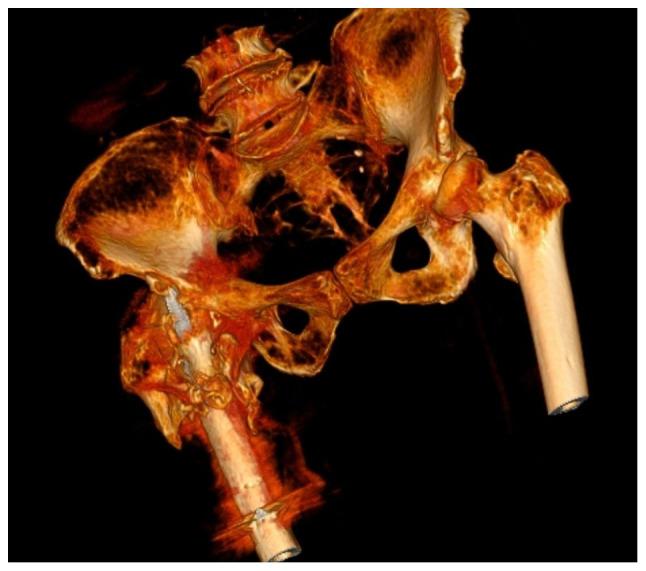

Uncommon causes of nail failures and surgical reinterventions were determined. The study included 23 osteoporotic patients, 13 of whom followed a fast recovery program with early walking (FWB group). The other 10 patients were not allowed full weight bearing until 6 weeks (NFWB group). The T-score was determined before surgery for all cases. A case with a nail breakage after a failed DCS implant fixed in another clinic was also analyzed. The nail was revised and the broken implant underwent a metallurgic and microscopic examination. The average T-score was 2.5 for the patients that followed the fast recovery program and 2.7 for the patients from non-full weight bearing. Four patients, 1 from the NFWB group and 3 from FWB group, presented a screw cut-out. It was found that the errors of the guiding instruments may create dents, scratches or micro-fractures on the titanium coating that lead to an early implant failure. Imperfect reduction leads to incorrect implant placement and a high incidence of failure. Damaging the titanium protective coating, in a low force, high cycles scenario can cause structural failure. Delays in fracture healing and material fatigue are the most common causes of nail failure and can lead to catastrophic complications.

确定了钉失败和手术再次干预的罕见原因。该研究纳入了23名骨质疏松患者,其中13名遵循快速康复计划并早期负重行走(早期负重行走组)。另外10名患者直到6周后才允许完全负重(非完全负重组)。对所有病例在手术前测定T值。还分析了1例在另一家诊所植入失败的DCS钉断裂的病例。对钉进行了翻修,并对断裂的植入物进行了金相和显微镜检查。遵循快速康复计划的患者平均T值为2.5,非完全负重患者的平均T值为2.7。4名患者出现螺钉穿出,其中1名来自非完全负重组,3名来自早期负重行走组。发现导向器械的误差可能在钛涂层上造成凹痕、划痕或微骨折,从而导致植入物早期失败。复位不完善会导致植入物放置不正确和高失败率。在低力、高循环情况下损坏钛保护涂层会导致结构失效。骨折愈合延迟和材料疲劳是钉失败的最常见原因,可导致灾难性并发症。